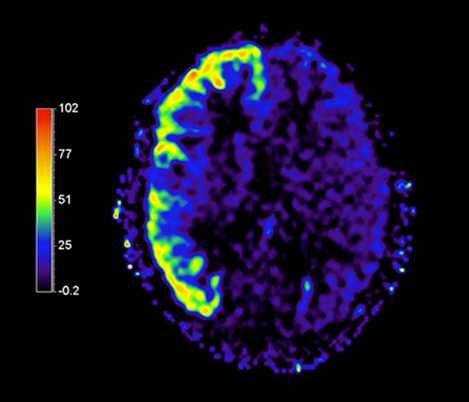

3 Compressed SENSE and APT are work in progress and not for sale in the USA

APT** and REACT**: The next steps towards non-invasive imaging strategies for pediatric MRI

Jeffrey H. Miller, MD

Vice Chair of Radiology for Research and Academic Affairs, Phoenix Children’s Hospital, Phoenix, AZ, USA